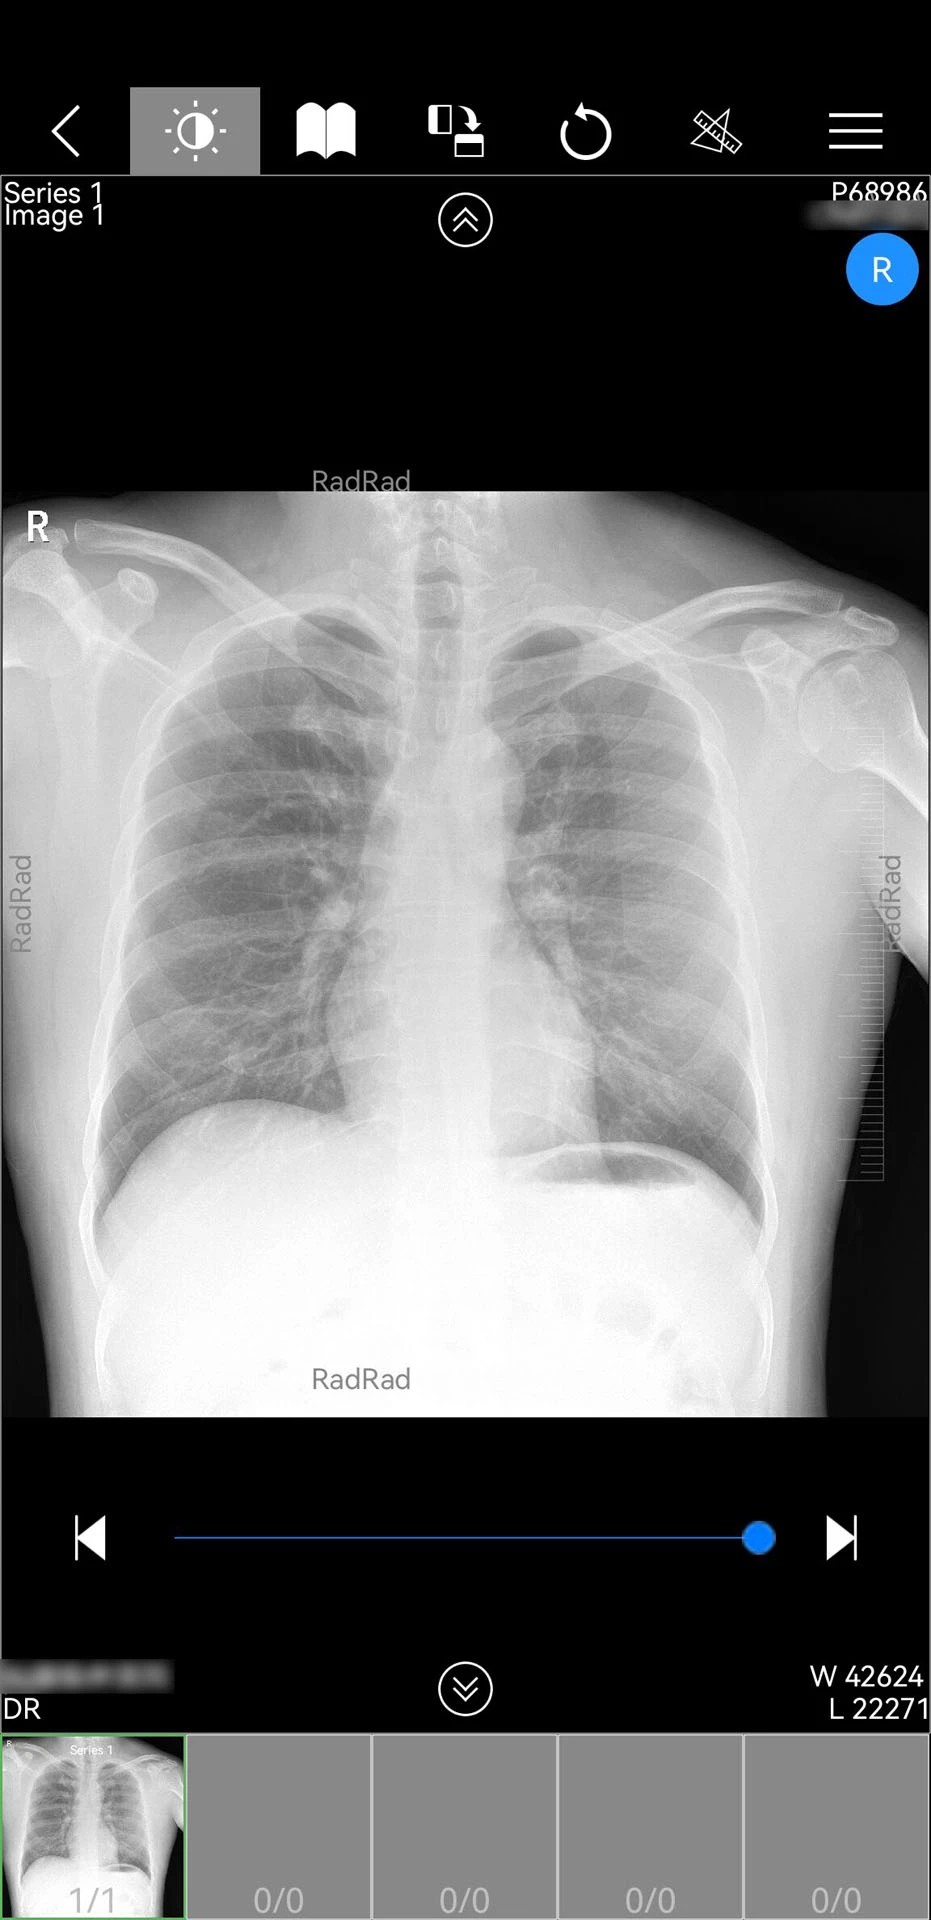

1. 影像处理能力突出:支持CT三维重建、多序列影像同步对比等高级功能,医生可自由缩放、旋转影像模型,精准定位病灶细节。例如,在肺部结节诊断中,通过三维重建可清晰观察结节与血管的空间关系,辅助制定手术方案。